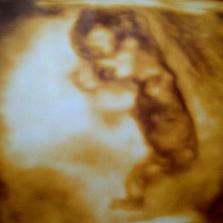

Tak to vše začalo.....